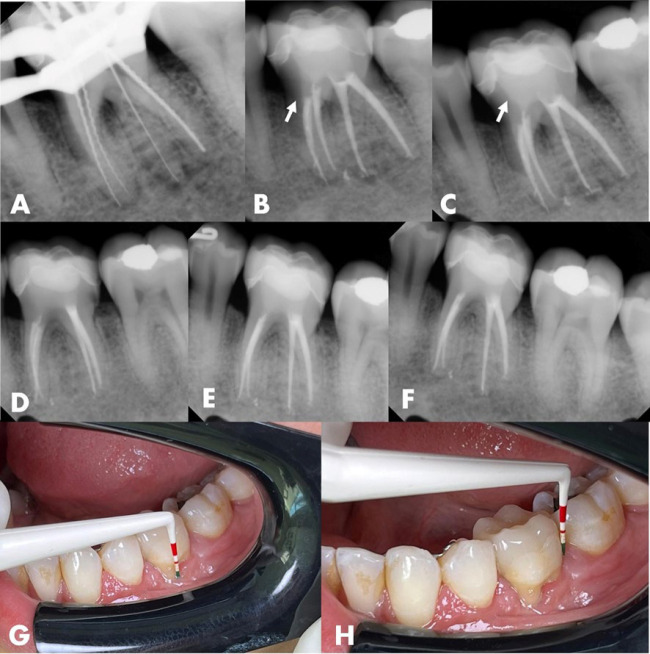

本病例报告强调了Biodentine作为一种孔内屏障的创新应用,用于治疗牙周内病变伴牙根延伸的牙裂。一名37岁女性患者报告咀嚼第36颗牙齿时疼痛。中牙根周围有明显的牙周附着物丧失。牙齿被诊断为牙髓坏死。在根管通道上,观察到一个垂直的裂缝延伸到中管壁。使用旋转器械确定和塑造根管。放置氢氧化钙作为管内敷料。一周后,患者无炎症症状返回。根管内填充了杜仲胶和生物陶瓷水泥。在孔口外2.0 mm处应用生物牙牙素修复水泥来密封和加固该区域。采用复合树脂修复根管通道腔。12个月的临床和影像学随访显示明显的根尖周愈合和无炎症体征。48个月的x线摄影和计算机断层扫描证实了骨修复和牙齿功能的持续。Biodentine的孔内屏障显示出显著的有效性,与文献中关于其益处的报道一致。该方案结合现代技术和及时修复,在处理牙根延伸的牙裂,加强复杂病例的牙齿保存方面显示出希望。

This case report highlights the innovative application of Biodentine as an intraorifice barrier in the management of cracked teeth with radicular extension associated with endo-periodontal lesions. A 37-year-old female patient reported pain during chewing on tooth #36. Significant periodontal attachment loss was noted around the mesial root. The tooth was diagnosed with pulp necrosis. Upon endodontic access, a vertical crack extending into the mesial canal walls was observed. Root canals were identified and shaped using rotary instruments. Calcium hydroxide was placed as an intracanal dressing. After one week, the patient returned without inflammatory signs. The root canals were filled with gutta-percha and bioceramic cement. Biodentine repair cement was applied 2.0 mm beyond the orifice to seal and reinforce the area. The endodontic access cavity was restored with composite resin. Clinical and radiographic follow-ups at 12 months revealed significant periapical healing and the absence of inflammatory signs. A radiographic and computed tomography scan at 48 months confirmed substantial bone repair and continued tooth functionality. The intraorifice barrier with Biodentine demonstrated notable effectiveness, aligning with literature on its benefits. The protocol, integrating modern techniques and timely restoration, shows promise in managing cracked teeth with root extension, enhancing tooth preservation in complex cases.